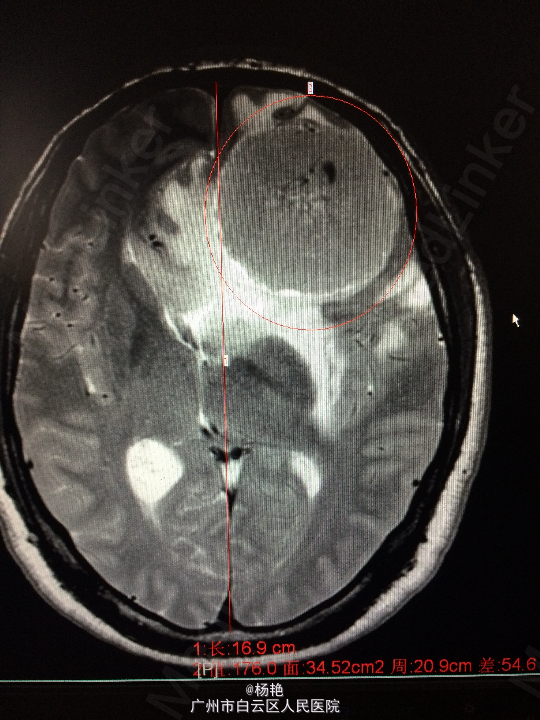

主诉:反复头痛2年加重1周 病史:患者诉两年前无明显诱因反复出现头晕头痛不适,近一周来症状加重,无恶心呕吐、无行走不稳、肢体乏力、意识障碍等。遂至当地医院诊治,行头颅CT、MR检查均提示颅内占位,良性可能性大,考虑脑膜瘤。今患者为求进一步治疗而入我院。

查体:神经系统查体未见明显异常 辅助检查:头颅MR提示:左侧额叶区域较大类圆形肿物,多考虑脑膜瘤可能;大脑前动脉及中动脉受压,中线偏移。

诊断:左额叶脑膜瘤 处理:在静脉全麻下行左侧额底脑膜瘤切除术,术后病理提示:脑膜瘤